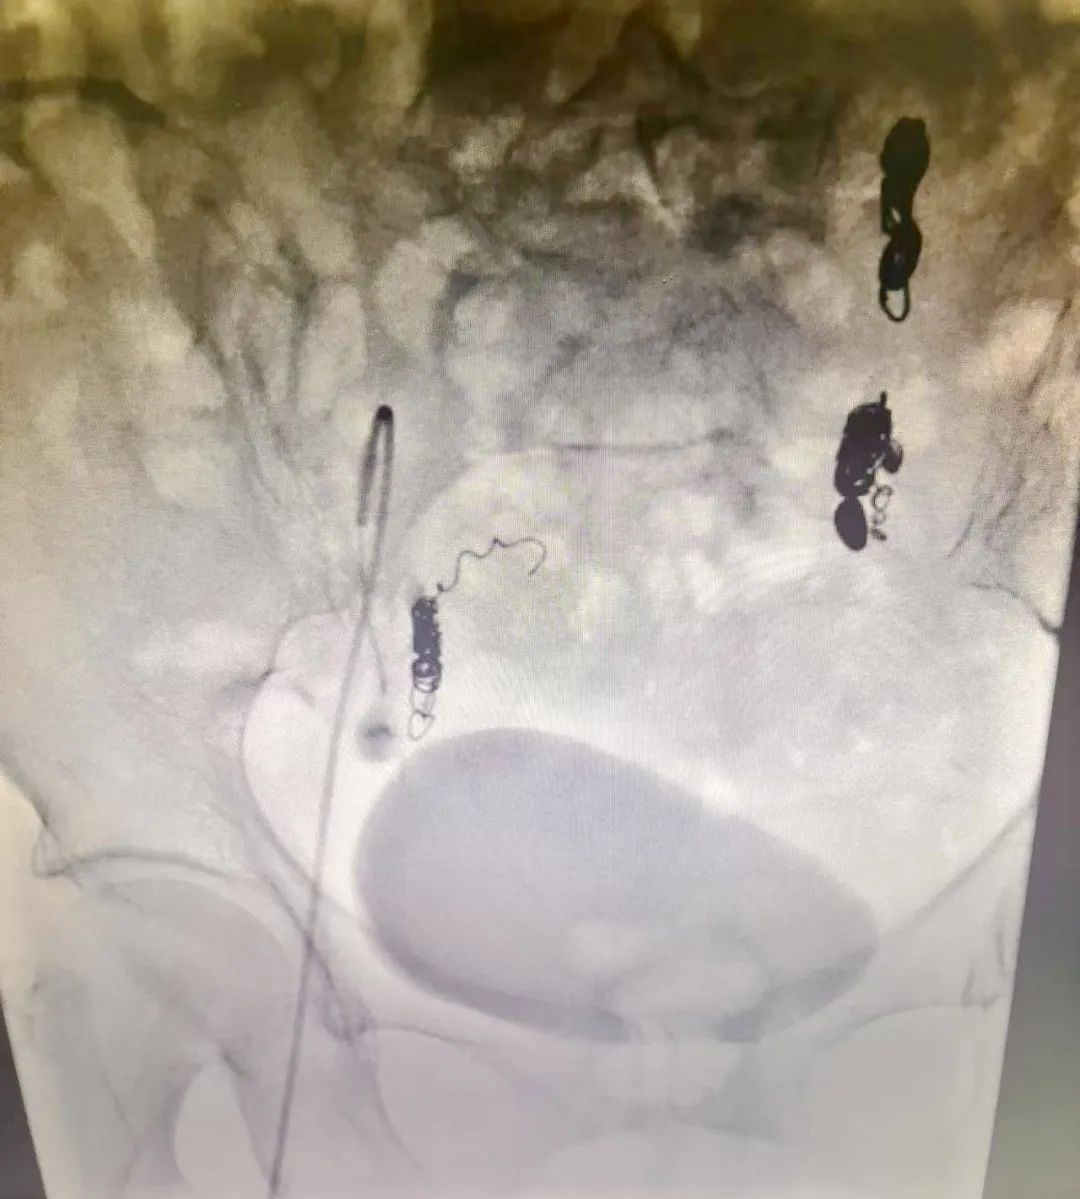

我科积极进行术前准备,完善患者的术前检查,择期安排患者行介入手术治疗,术中造影显示盆腔静脉迂曲扩张并有丰富的交通支。

术中找到并弹簧圈栓塞迂曲扩张的左侧卵巢静脉,并栓塞右侧迂曲扩张的子宫静脉,栓塞后再次造影,未见造影剂滞留。